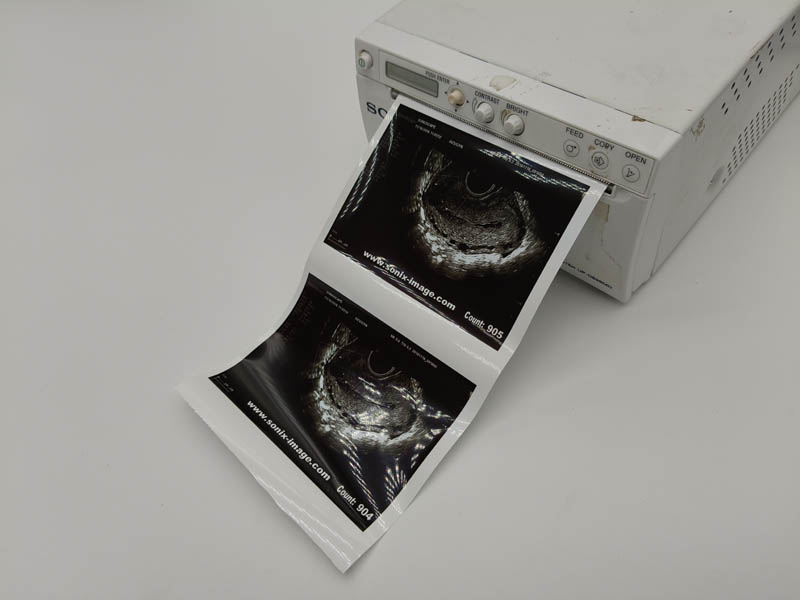

Ultrasound Paper Rolls UPP-110HD_Type II

PRODUCT INTRODUCTION

Ultrasound thermal paper roll

1. Original place:Japan

2. Use in medical video Printers

3. Top quality

4. Size: 110mm*18m

5. OEM is acceptable

Thermal Video Printer Paper

Japanese origin.

1.Glossy Type Paper(Type V).

2.Each roll is packed in individual pack

3.High resolution and preservation of printed video image

4.110S,110HG,110HD

5.Package: 10 rolls/box, 10boxs/cartons